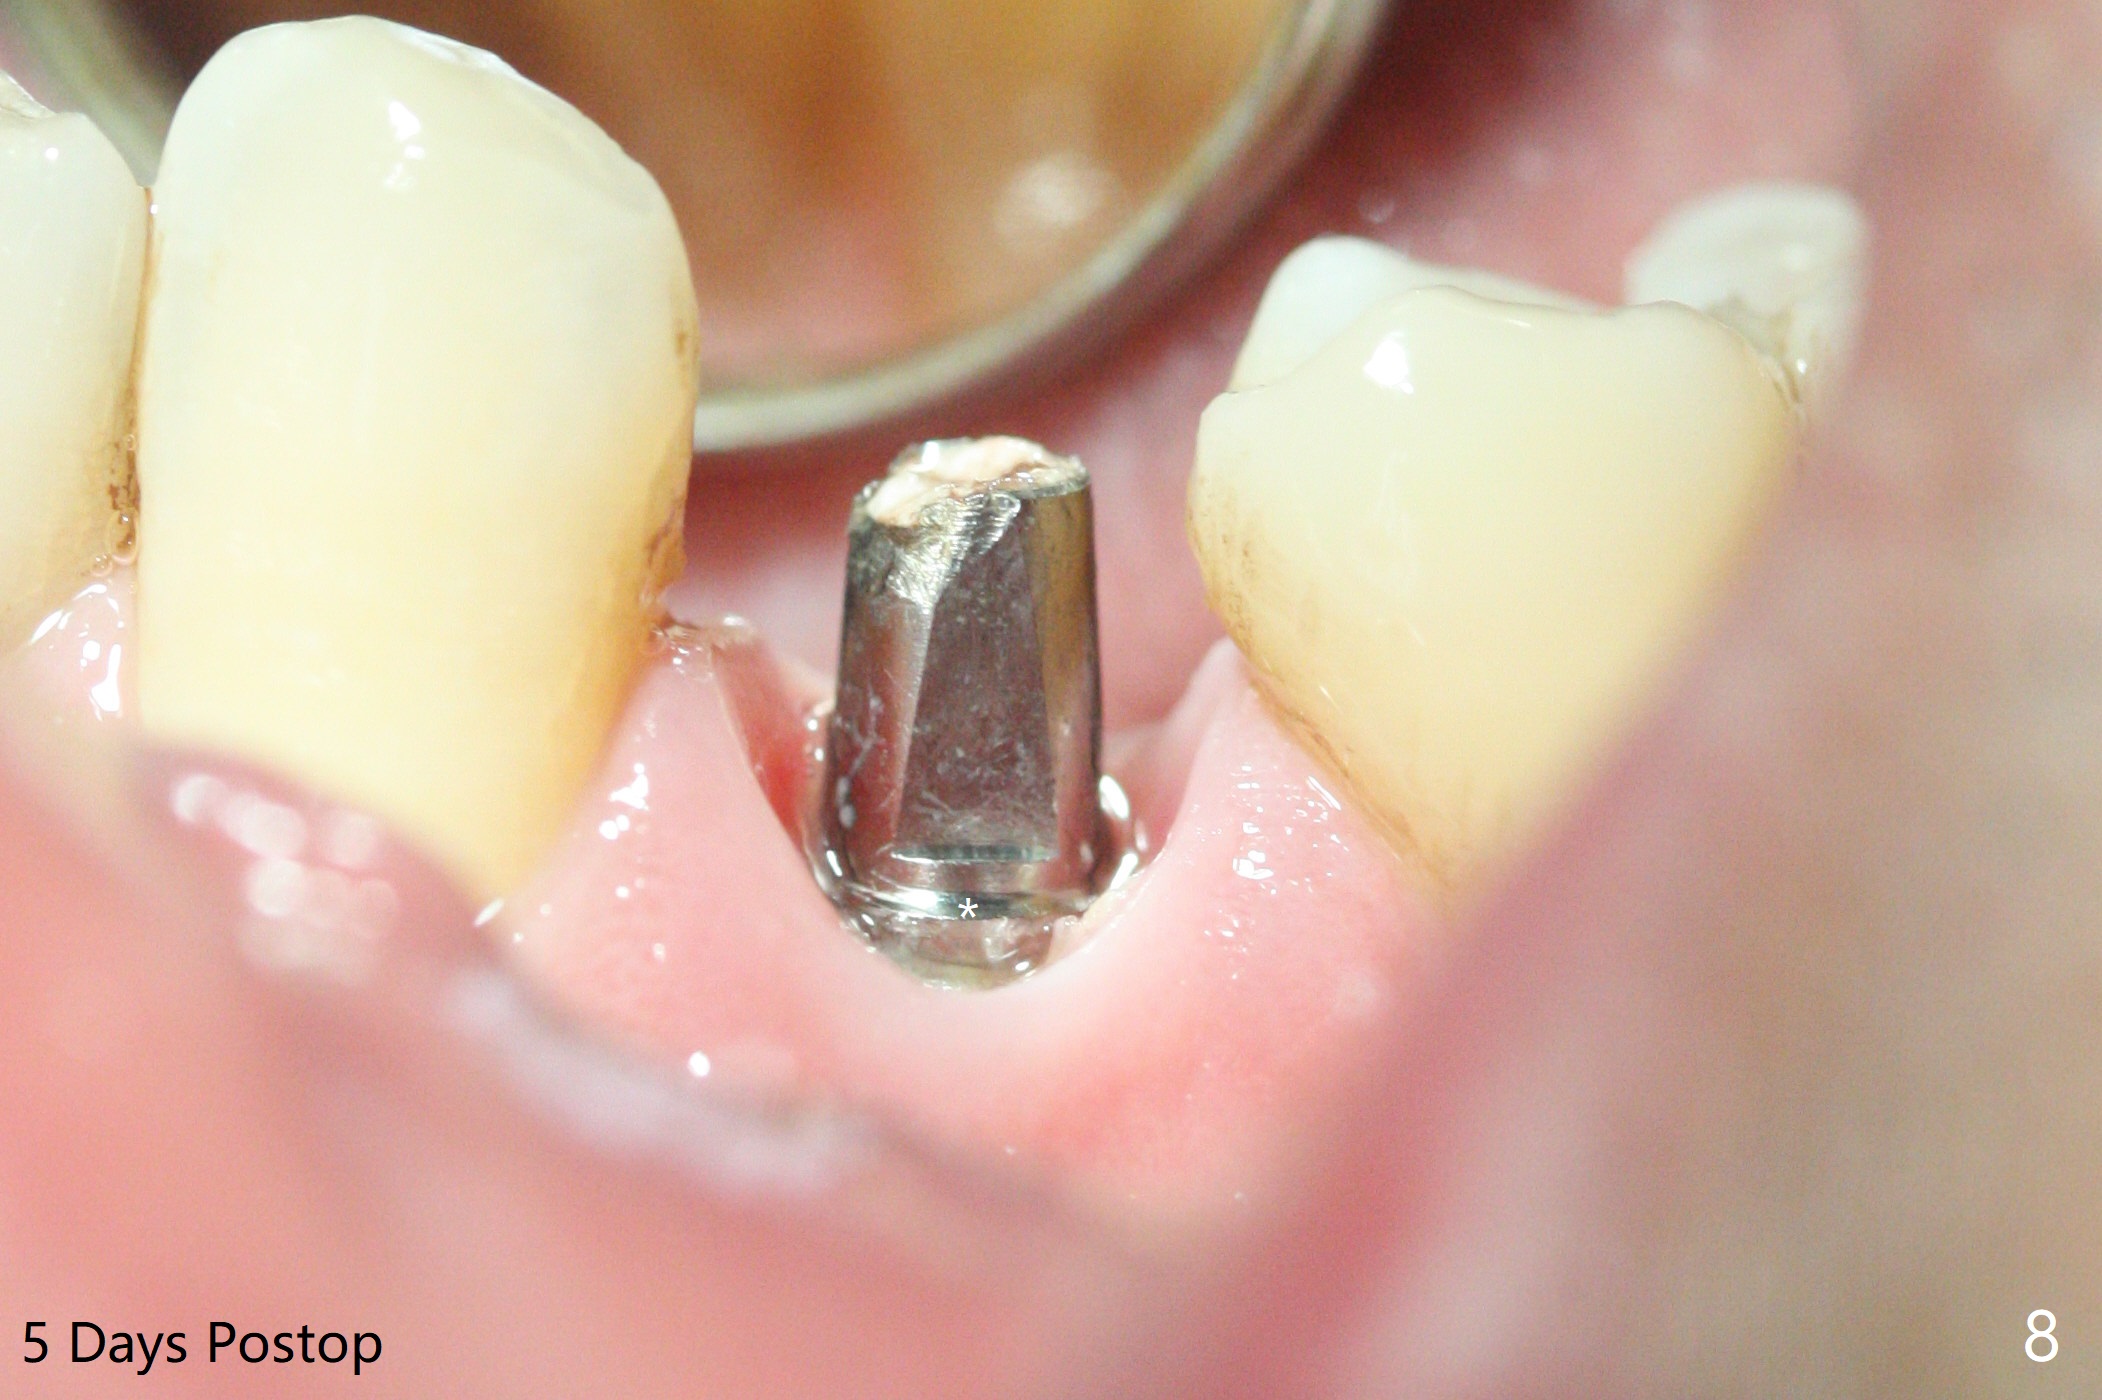

Three months post guide fabrication (coronavirus outbreak), the patient with loose post/crown returns for #21 extraction and immediate implant with guide (Fig.1 (*: post space)). In fact the root stump is flattened with diamond bur and 9 mm bone trimmer with guide before point drill. When the osteotomy finishes with 3.5x13 mm drill (under drilling with 10.5 mm offset), it has deviated buccal (Fig.2, 3,4); the outline of the bone trimmer mark is labeled by arrowheads in Fig.2. It appears that the center of the bone trimmer is dictated by that of the post space, as compared to Fig.1 *). When the root is removed except buccal shield (assuming that the deviation was due to the uneven surface of the root stump), the osteotomy is redone with guide, but remains buccal. Finally with buccal shield removal, a new lingual osteotomy is created free hand for a 4.5x11 mm implant (Fig.5) with 2-3 mm buccal gap for bone graft (Fig.6 * (literally)). In brief, bone trimmer also deviates according to resistance, basically irrelevant to the guide sleeve. The immediate provisional is intentionally removed 5 days postop to check whether a piece of gauze is retained in the socket as a gingival retraction cord for temporary crown fabrication; the buccal gap is kept with bone graft (Fig.7 *). No foreign body is in place. The margin of the abutment seems quite subgingival (Fig.8 *), but re-trimmed and polished provisional looks harmonious with the surrounding gingiva and the opposing dentition (Fig.9,10). The patient returns for prophy 2 months postop; the immediate provisional is removed for trimming and polishing. The bone graft seems to be integrated into a part of the gingiva (Fig.11 >). The abutment cuff appears to be too short.